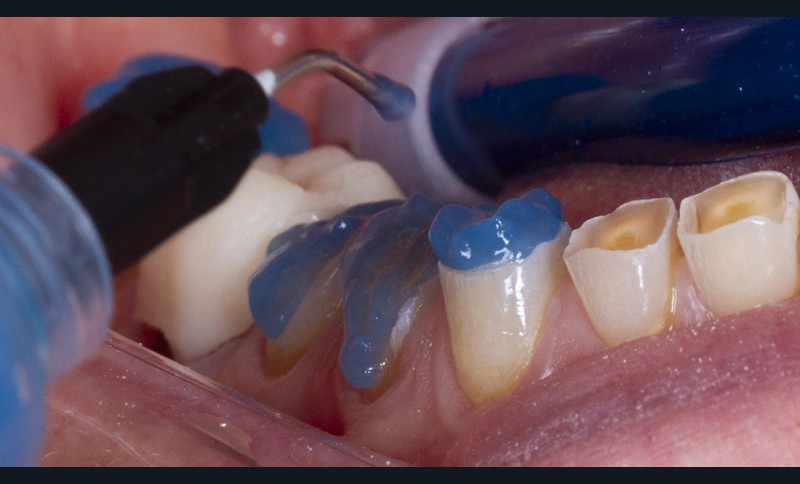

Dans un deuxième temps, un wax-up global permet de restaurer les courbes d’occlusion. Il est à noter que la présence d’égressions dentaires, faute d’antagoniste ou d’anciennes restaurations prothétiques inadaptées, crée des usures inégales au sein de la cavité buccale. Aussi, la présence de zones non recouvertes par le wax-up dans les secteurs postérieurs est courante, permettant ainsi la préservation de zones amélaires majeures pour le collage (fig. 2).

Le wax-up est le point de départ pour la réalisation de temporisations en technique d’isomoulage. Pour cela, le repositionnement de la clé en silicone s’effectue grâce à la réalisation de butées d’enfoncement sur des zones non waxées ou volontairement déwaxées (fig. 3).